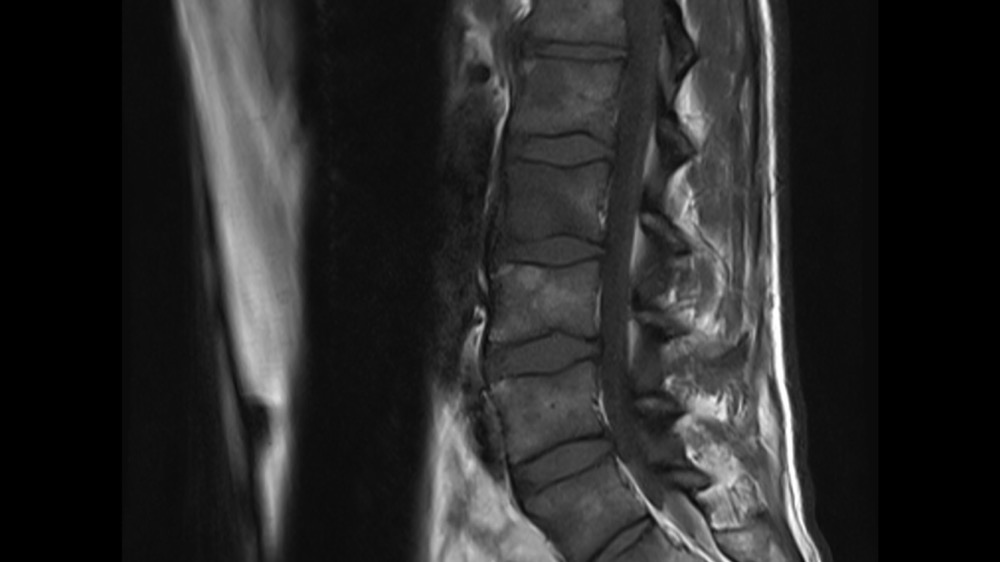

Constance du Boisbaudry 19/01/2022